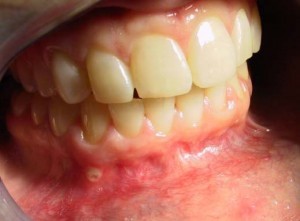

A Typical Minor Aphthous Ulceration

Minor Aphthous Stomatitis: this is the form that affects more than 80% of canker sore sufferers. The sores are usually small (less than 1 centimeter in diameter), heal in about a week, and do not cause scarring.